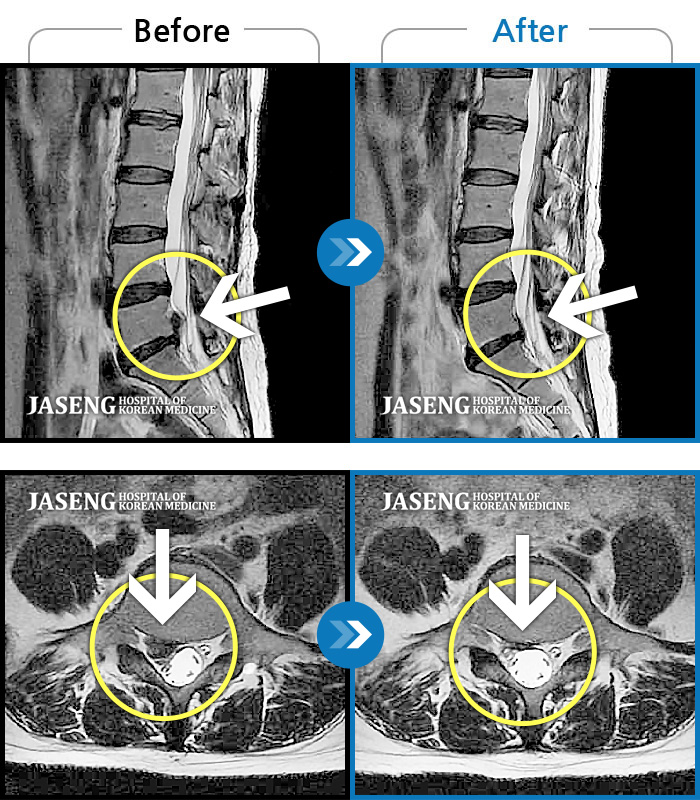

허리디스크

많이 본 사례

수원 · 김태성 원장

허리 통증과 좌측 대퇴부 저림과 당김

촬영시기

2023.02.03 ~ 2024.02.14

2024.11.21